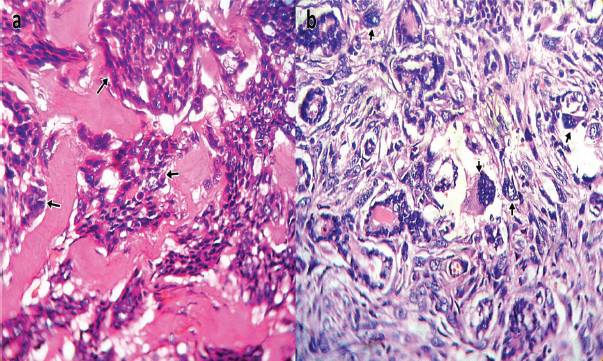

Sixty-one (61) cases of TCs were identified in this study constituting 10.8% (61/564) of thyroidectomy specimens received at our hospital’s Morbid Anatomy Department during the 15 year period under review. There were 51 (83.6%) females and 10 (16.4%) males giving a ratio of 5.1:1, and a mean age of 45.9 years [Table/Fig-1]. The most common histologic type was papillary thyroid carcinoma 26 (42.6%) cases [Table/Fig-2], followed by follicular carcinoma 23 (37.7%) cases [Table/Fig-3], medullary thyroid carcinoma 3 (4.9%) cases [Table/Fig-4a], anaplastic carcinomas 2 (3.3%) cases [Table/Fig-4b], Non-Hodgkin lymphoma 1 (1.6%) case and metastatic squamous cell carcinoma 2 (3.3%) cases. Three (4.9%) cases of mixed follicular/papillary carcinoma and one (1.6%) case of mixed papillary/anaplastic carcinoma were also identified in this study.

Photomicrograph of: (a) Medullary carcinoma of the thyroid showing paragangliomatous and pseudopapillary growth patterns [short arrows] (H & E Stain X400); (b) Anaplastic carcinoma of thyroid, giant cell type showing tumor giant cells with bizarre hyperchromatic nuclei [short arrows] (H & E Stain X400).

Medullary carcinoma is still relatively uncommon with only 3 (4.9%) cases identified in our study which is in agreement with findings from Port-Harcourt (one case), Ile-Ife (one case), Zaria (three cases) and Lagos (four cases) in Nigeria [11,13,16,21] as well as reports from Ethiopia (one case) [22] and Pakistan (four cases) [25].

Our study also recorded only 2 (3.3%) cases of anaplastic carcinoma. This is similar to those of studies in Port-Harcourt, Kano, Ile-Ife and Lagos that also reported 1-2% cases [11-13,16]. This rare type of TC often presents with a fatal disease course despite aggressive treatment modalities of surgery, chemotherapy, and radiotherapy, in contrast to the excellent prognosis of individuals diagnosed with DTC [31]. Two (3.3%) cases of metastatic squamous cell carcinoma were also noted in our study which is consistent with the finding of one case in a recent study in Kano [32]. Similarly, only 1 (1.6%) case of Non-Hodgkin lymphoma was discovered in our study.